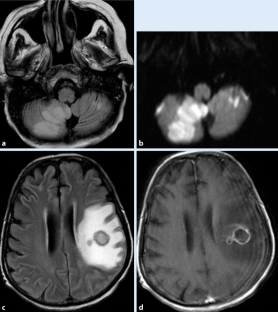

Abb. 1